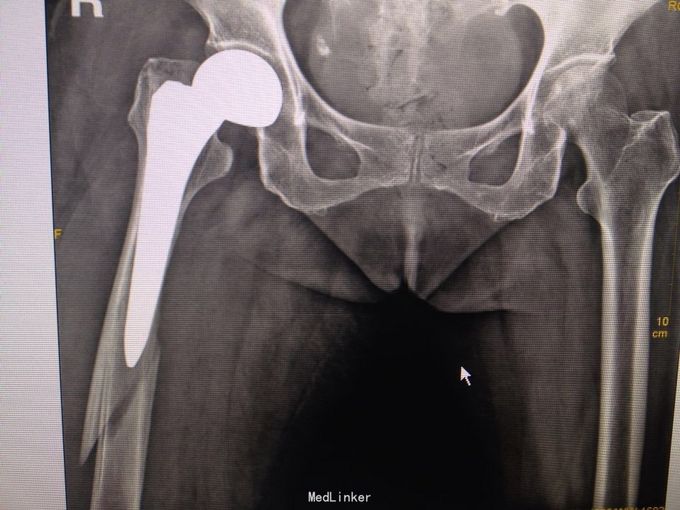

患者84岁女性,4周前因右股骨颈骨折行人工股骨头置换术,术顺,恢复佳,4天前摔倒,致右大腿肿痛,立行不能

右髋部手术瘢痕,无破皮出血及骨质外露,右股骨中段压痛,右股骨纵向叩痛阳性,末端血运感觉好。 X线提示右股骨中段骨折,上段见人工股骨头置换术后,

右股骨头置换术后股骨假体周围骨折(B3) 行右人工股骨头置换术后假体周围骨折切开复位记忆合金钢板+钛缆绑带固定术